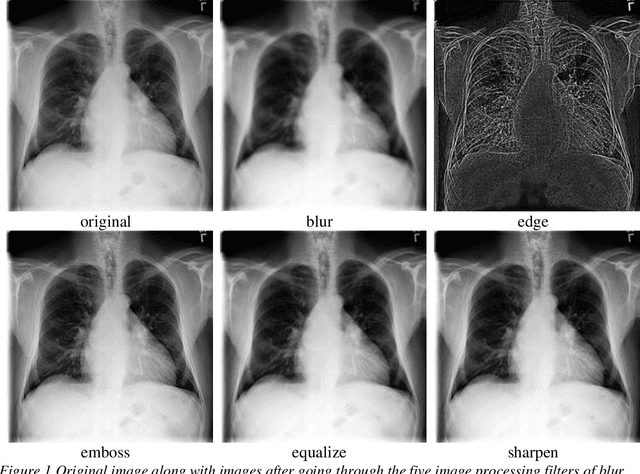

Purpose: The purpose of this study was to observe change in accuracies of convolutional neural networks (CNN) models (ratio of correct classifications to total predictions) on thoracic radiological images by creating different binary classification models based on age, gender, and image pre-processing filters on 14 pathologies. Methodology: This is a quantitative research exploring variation in CNN model accuracies. Radiological thoracic images were divided by age and gender and pre-processed by various image processing filters. Findings: We found partial support for enhancement to model accuracies by segregating modeling images by age and gender and applying image processing filters even though image processing filters are sometimes thought of as information filters. Research limitations: This study may be biased because it is based on radiological images by another research that tagged the images using an automated process that was not checked by a human. Practical implications: Researchers may want to focus on creating models segregated by demographics and pre-process the modeling images using image processing filters. Practitioners developing assistive technologies for thoracic diagnoses may benefit from incorporating demographics and employing multiple models simultaneously with varying statistical likelihood. Originality/value: This study uses demographics in model creation and utilizes image processing filters to improve model performance. Keywords: Convolutional Neural Network (CNN), Chest X-Ray, ChestX-ray14, Lung, Atelectasis, Cardiomegaly, Consolidation, Edema, Effusion, Emphysema, Infiltration, Mass, Nodule, Pleural Thickening, Pneumonia, Pneumathorax